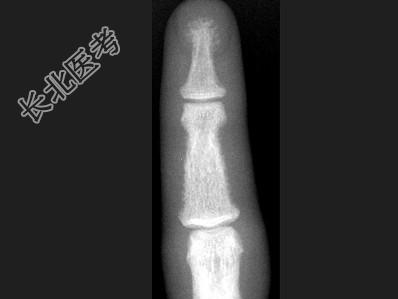

- 单项选择题女,41岁, 慢性肾功能不全,结合图像, 最可能的诊断是 ( )

B、甲状旁腺功能亢进